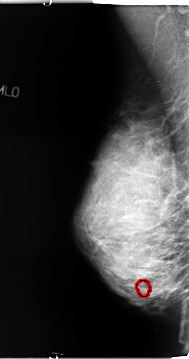

B_3127_1.RIGHT_CC

FILE: B_3127_1.RIGHT_CC.OVERLAY

TOTAL_ABNORMALITIES 1

ABNORMALITY 1

LESION_TYPE CALCIFICATION TYPE PLEOMORPHIC DISTRIBUTION CLUSTERED

ASSESSMENT 4

SUBTLETY 3

PATHOLOGY BENIGN

TOTAL_OUTLINES 1

BOUNDARY